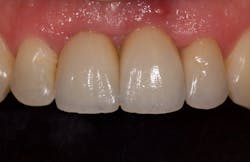

I began centering my consultation appointments on options that subsequently allowed patients to actually sell themselves on the implant treatment modality. I would present the tooth-replacement options of endo/core/crown, extraction/bridge, and extraction/implant ... and then I would explain the pros and cons of each. What I found is that patients overwhelmingly chose the root-replacement option—dental implants—over the old-school (drill-o-dontics) to reconstruct their missing tooth. Patients actually wanted an implant once they were armed with all the complete information they needed to make their decision. Having models on hand that show the difference between each option is highly effective, especially for those patients who are visual learners.

When your treatment plan includes only the next most conservative procedure—instead of all treatment options—inevitably you will do lots of work “saving” badly damaged roots and roots with guarded or poor long-term prognosis. Some patients may applaud or highly value these efforts on your part, but I have met many more who are glad to skip the possibility of re-treatment, root fracture, core failure, etc. You'll find that many patients will choose implants as an expedient and efficacious alternative to restoring the root with diminished or guarded prognosis, rather than spend their money over and over again on an undesirable tooth.

This is the paradigm shift in thinking that initiated big changes in my practice. In 2010, my little office restored 38 implant fixtures. By 2017, we were restoring closer to 200. What a difference! When patients began to realize they had treatment possibilities that may have a better long-term prognosis than the traditional replacement options, implants became a definite green light for them.